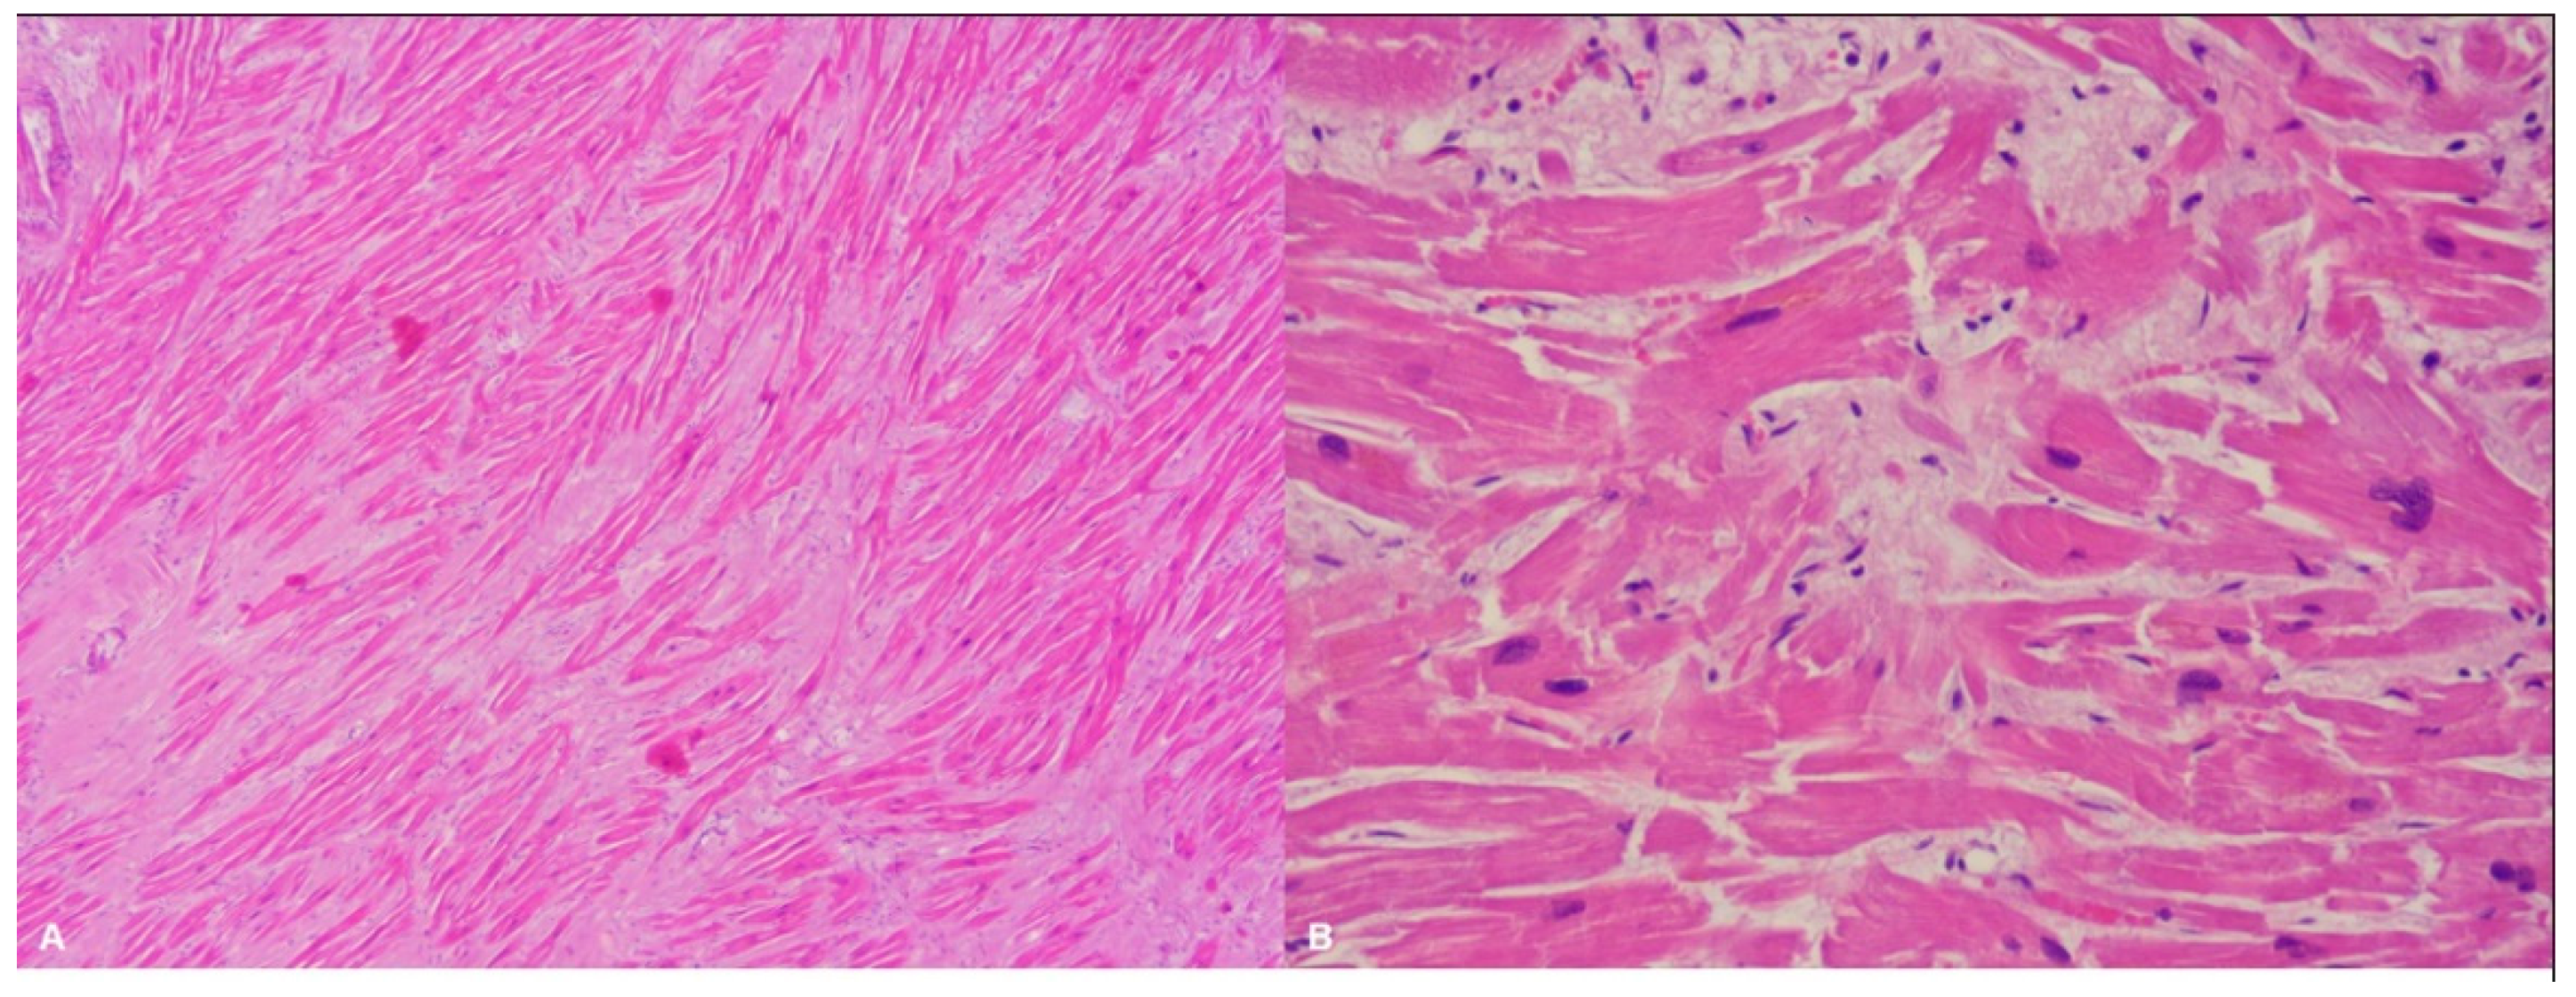

| Typical histopathological features | Myocytes hypertrophy, disarray, thickened intramural arterioles with luminal narrowing, myocardial fibrosis [102,103] | Fibrofatty replacement of the ventricular myocardium with a subepicardial-mid-mural or transmural distribution [54] | Replacement fibrosis, interstitial fibrosis, atrophied and/or hypertrophied cardiomyocytes, nuclear pleomorphism [82] |